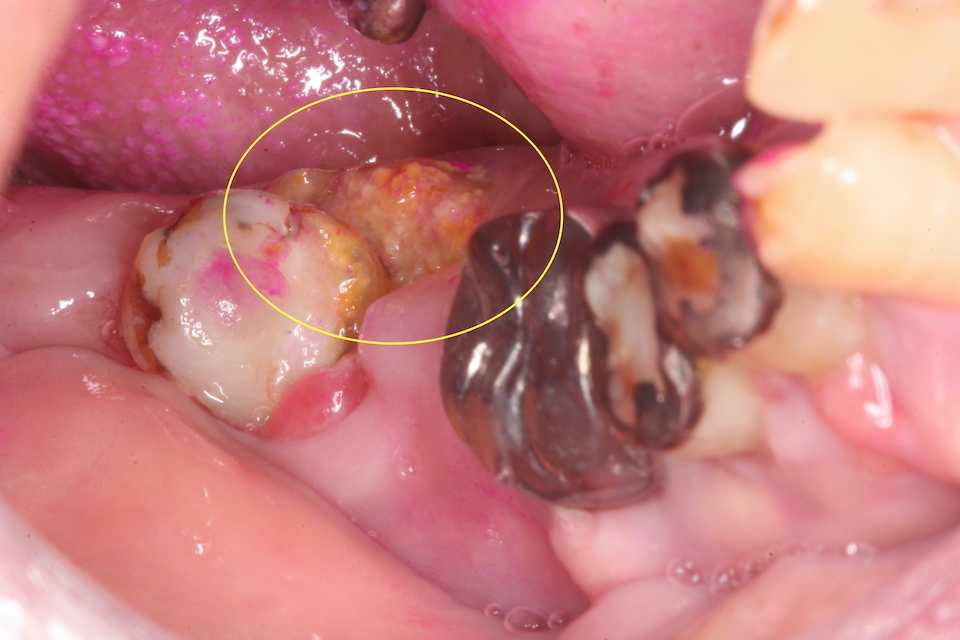

70代女性、右下7、咬合性外傷による歯髄壊死、自発痛+レントゲン写真を見ると根尖付近の陰影が強いので歯髄は壊死している可能性が高いことがわかる。このような症例は5分で終わることができて、しかも予後が極めて良い伝説の根管治療法を無料で完全公開しておきます。とりあえずインレーを除去して天蓋も除去して歯髄を見てみることにした。超音波スケーラーのエンドチップ#20 21mmで根管を洗浄。根管内の有機質を除去しようとか根管開拡しようとか、無駄どころか感染の機会を増やしてしまうことは一切必要ない。根管は水平エアブロウするだけで感染させるだけの乾燥工程は必要はない。1回目の3MIX+α-TCP精製水練りをディスポシリンジで充填し、エンドチップで押し込む。僕が使っているボンディング材はこちら。1回目のα-TCPは精製水練り。浸透性が良いが硬化が遅い3MIX+α-TCPを根管内に入れるだけで良い。緊密充填など考える必要はない。2回目はα-TCPの50%クエン酸練り(硬化する)。この上からCRダイレクトボンディングでカバーする。3MIXの作り方はこちら。α-TCPの入手法はこちら1回目2回目CRでカバーして終了。